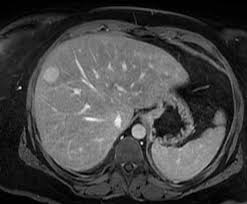

Abdomen Pelvis MRI Protocol

• Pre contrast LAVA/VIBE

• Post contrast Dynamic Abdomen LAVA/VIBE

• Post contrast Delay Abdomen & Pelvis